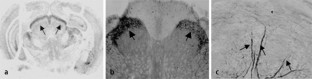

Abb. 1

Abb. 2

Abb. 3

Abb. 4

Abb. 5